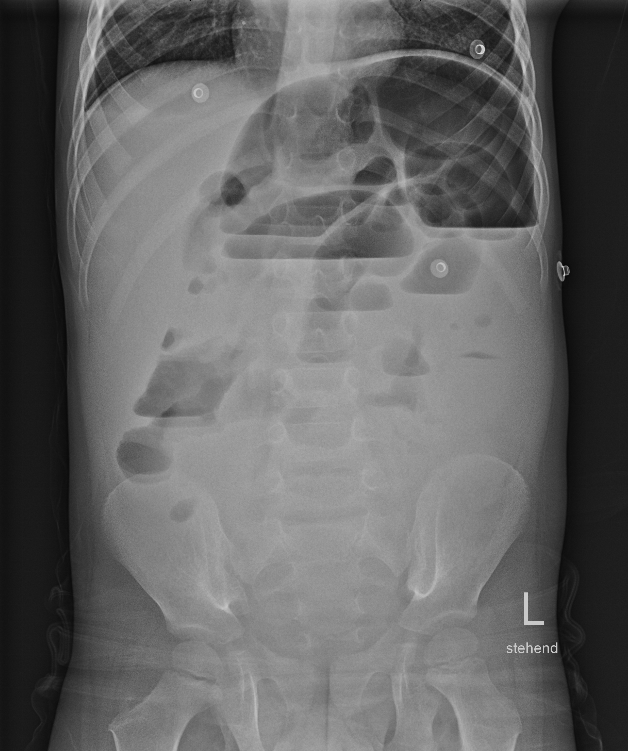

Morbus Hirschsprung

Beim Morbus Hirschsprung handelt es sich um eine angeborene Erkrankung, bei der die Nervenzellen in der Darmwand des Enddarms fehlen. Meistens ist das letzte Drittel des Dickdarms betroffen. Durch die fehlenden Nervenzellen zieht sich der betroffene Darmabschnitt zusammen und führt zu einer Störung des normalen Weitertransports des Stuhlgangs. Der Stuhlgang staut sich vor dem betroffenen Abschnitt an und führt zu einer Aufdehnung des Dickdarms („Megacolon“). Auffällig werden diese Kinder teilweise direkt nach der Geburt durch fehlendes Absetzen des ersten Stuhlgangs („Mekonium“) oder im Säuglings- und Kleinkindalter durch eine chronische Verstopfung. Die Symptome können so stark sein, dass sie einem Darmverschluss ähneln. Eine bakterielle Überwucherung des aufgestauten Stuhlgangs kann zu einem mitunter lebensbedrohlichen Zustand führen („toxisches Megacolon“).

Diagnostik- und Therapiekonzept

Sollte Ihr Kind direkt nach der Geburt Auffälligkeiten zeigen, werden wir zur Mitbeurteilung auf die Entbindungsstation oder auf die Neugeborenenstation hinzugezogen. Sollten sich erst zu einem späteren Zeitpunkt Symptome zeigen, die an einen Morbus Hirschsprung denken lassen, erfolgt meist eine Vorstellung in unserer kinderchirurgischen Sprechstunde. Wir bitten Sie zu diesem Termin bereits vorhandene Untersuchungsergebnisse (z.B. Ultraschall, Laborwerte, Ergebnisse aus anderen Krankenhäusern) mitzubringen. Wir werden dann entscheiden, welche weiteren Untersuchungen notwendig sind. Diese können eine Ultraschalluntersuchung des Bauches, eine Röntgen-Untersuchung des Dickdarms („Colon-Kontrast-Einlauf“) oder eine Gewebeentnahme aus der Schleimhaut des Dickdarms zur mikroskopischen Untersuchung beinhalten. Letztere ist der Goldstandard zur Diagnosesicherung eines Morbus Hirschsprung.

Die Diagnostik und Therapie erfolgt primär durch die Kolleg:innen der Neugeborenenintensivstation. Bei ersten Anzeichen werden die Patient:innen umgehend mit Antibiotika-Gaben behandelt. Zudem bleiben die Patient:innen nüchtern, um die betroffenen Darmabschnitte zu entlasten. In den Blutwertkontrollen kann die Entzündung abgelesen werden. Zudem erfolgen sonographische Kontrollen, die Gasbläschen in der Darmwand zeigen. Der Darm kann sich nicht mehr richtig bewegen, sodass die Nahrung nicht mehr richtig transportiert werden kann. In einem Röntgenbild vom Abdomen zeigen sich weite, ausgedehnte Darmschlingen. In manchen Fällen ist die Entzündung bereits so weit fortgeschritten, dass es zum Darmdurchbruch (Perforation) gekommen ist.